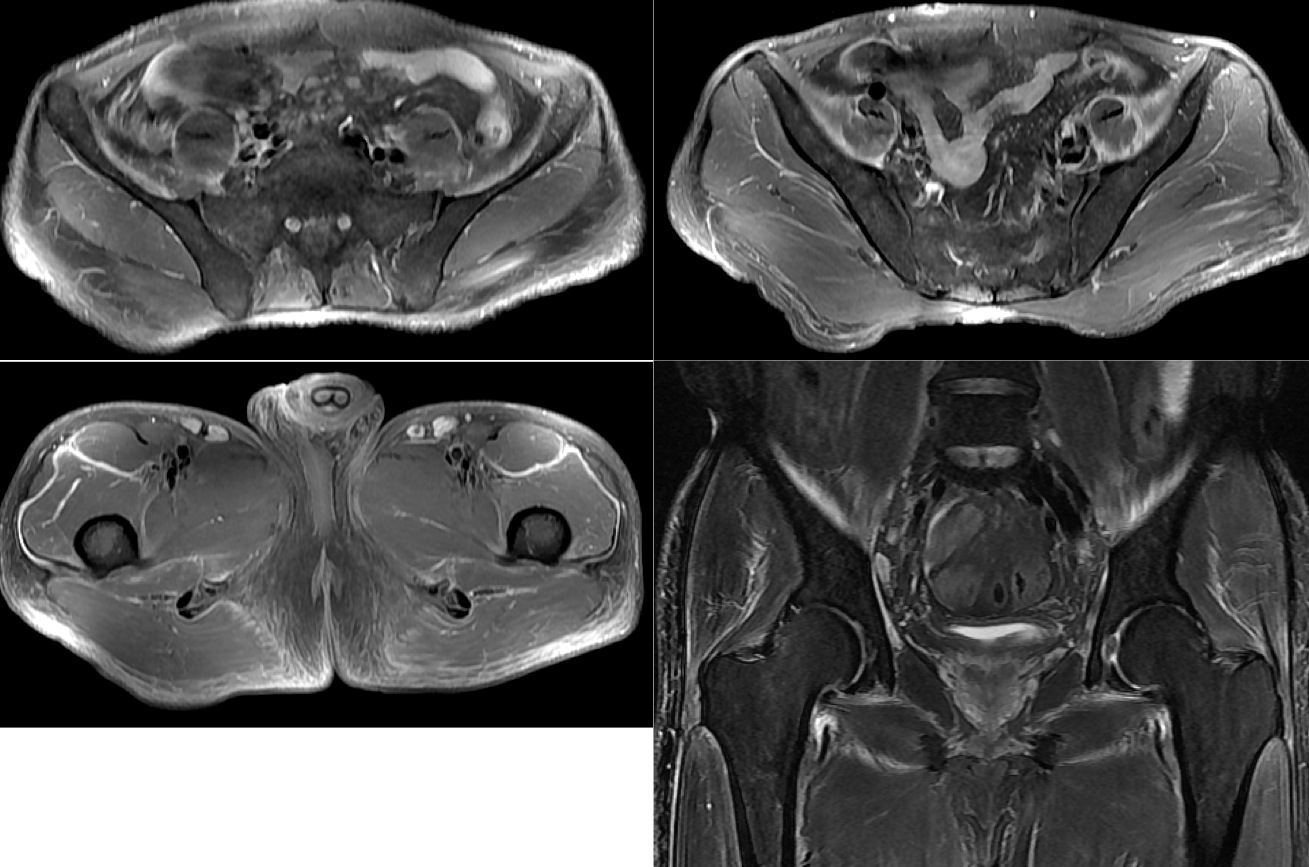

Figure 1 for case Systemic sclerosis with diffuse fascitiis

Figure 1